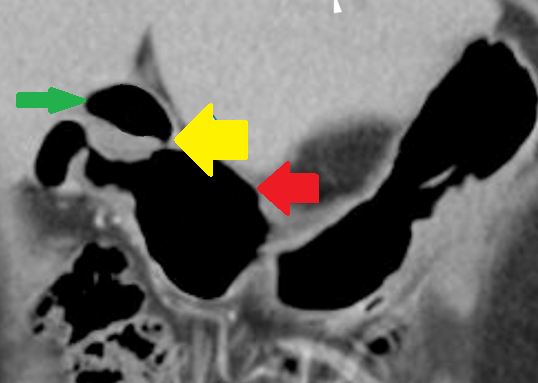

Upper gastrointestinal endoscopy showing a grossly deformed duodenal bulb. A steady trickle of bile was also seen to come from a slit-like orifice on the anterior duodenal wall suggestive of biliary duodenal fistula (green arrow)